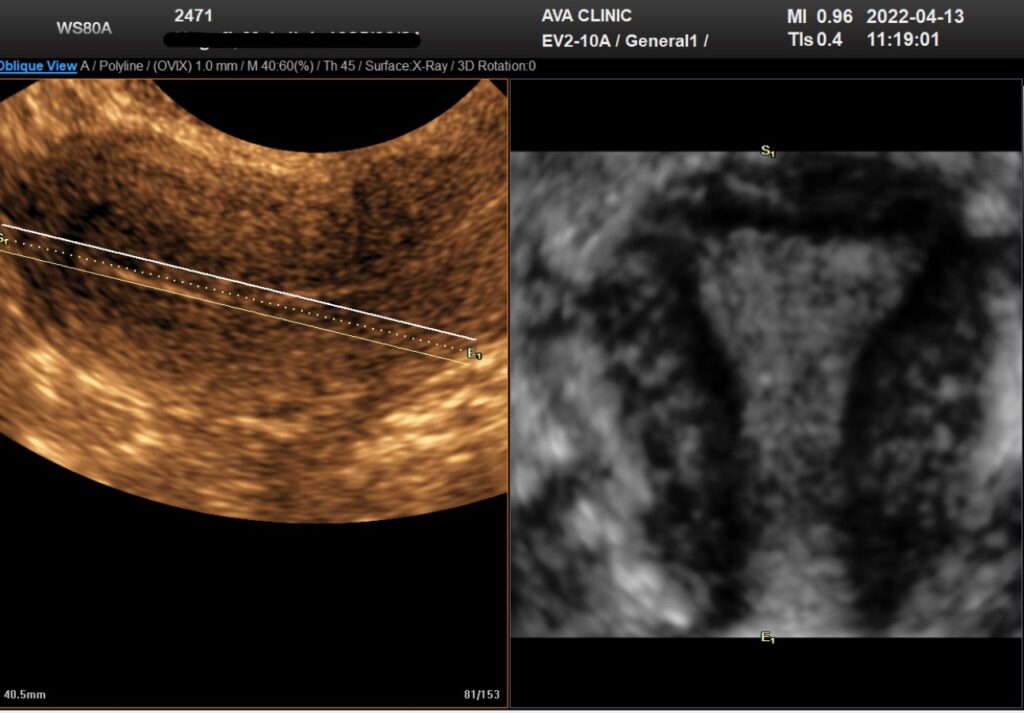

یکی از ویژگی های برجسته 3D USG توانایی آن برای به دست آوردن تصاویر در تجهیزاتی که قبلاً در دسترس نبودند با استفاده از 2D USG است. Coronal plane می تواند اطلاعات دقیقی در مورد رحم و آدنکس ارائه دهد و به ویژه در تشخیص ناهنجاری های مادرزادی رحم مفید است (شکل 1). به همین ترتیب، کف لگن را می توان به طور موثر در سطح محوری با استفاده از USG سه بعدی ارزیابی کرد. علاوه بر این، کاربر توسط این هواپیماهای معمولی محدود نمی شود. ساختن هر صفحه ای از داده های حجم به دست آمده امکان پذیر است.

تصویر سه بعدی از رحم طبیعی. نمای تاجی هم حفره رحم و هم کانتور خارجی رحم را به وضوح نشان می دهد